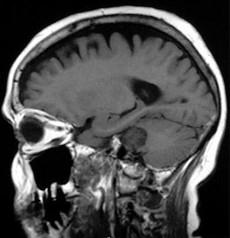

问题 有关听神经鞘瘤(如图所示)的发生,下列哪项描述不正确()

选项 A.多发生于听神经的内听道段或内耳孔区 B.听神经瘤起源于Schwann细胞 C.听神经瘤多来自耳蜗神经 D.大多数是单侧性 E.好发于中年人

答案 C